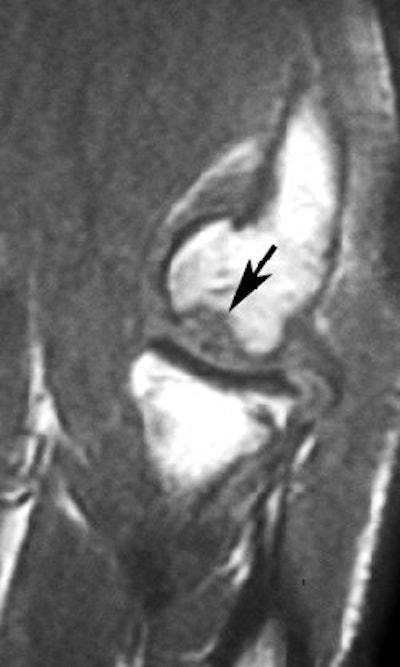

|  |

| Same patient as above. Top, sagittal T1-weighted MR image of elbow shows lesion (arrow) as large area of signal abnormality with low-signal-intensity rim and heterogeneous intermediate signal intensity and low signal intensity centrally. Below, sagittal fat-suppressed T2-weighted fast spin-echo MR image of elbow shows osteochondritis dissecans lesion (arrow) as large area of signal abnormality with high-signal-intensity rim and linear bands of high and low signal intensity centrally. Note marked irregularity of articular cartilage overlying osteochondritis dissecans lesion (arrowhead). |

| Kijowski R and De Smet AA, "MRI Findings of Osteochondritis Dissecans of the Capitellum with Surgical Correlation" (AJR 2005; 185:1453-1459). |